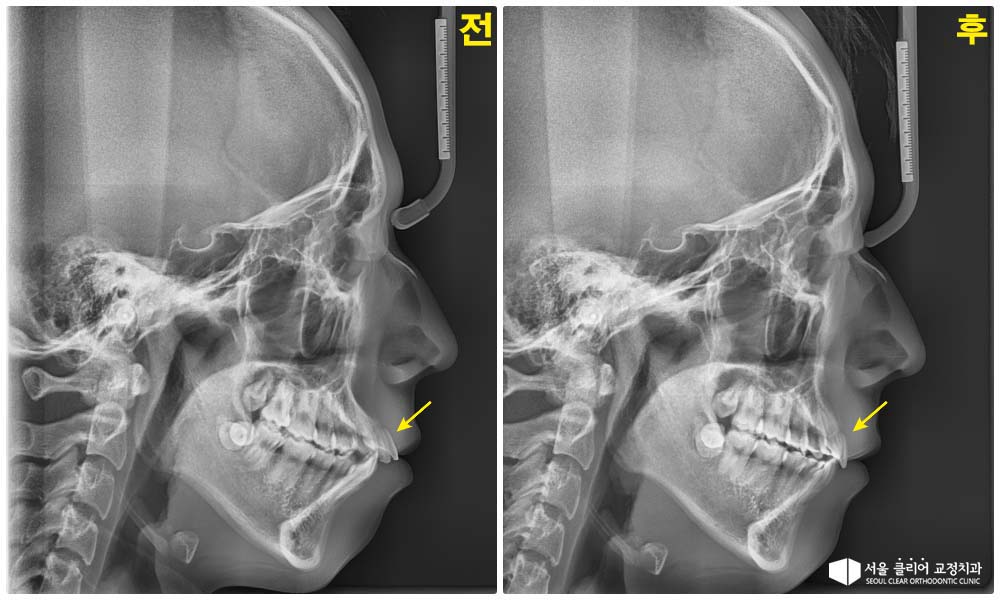

엑스레이 결과: 아래턱 발달 부족과 치아 경사가 겹쳐 입술 돌출감이 심한 상태

교정 치료 완료 후, 전방으로 쏠렸던 앞니 경사가 개선되었습니다.

외모 변화: 입술의 돌출감이 줄어들고, 턱 끝 연조직 라인이 부드러워지면서 자연스러운 옆모습(Profile)이 완성되었습니다.